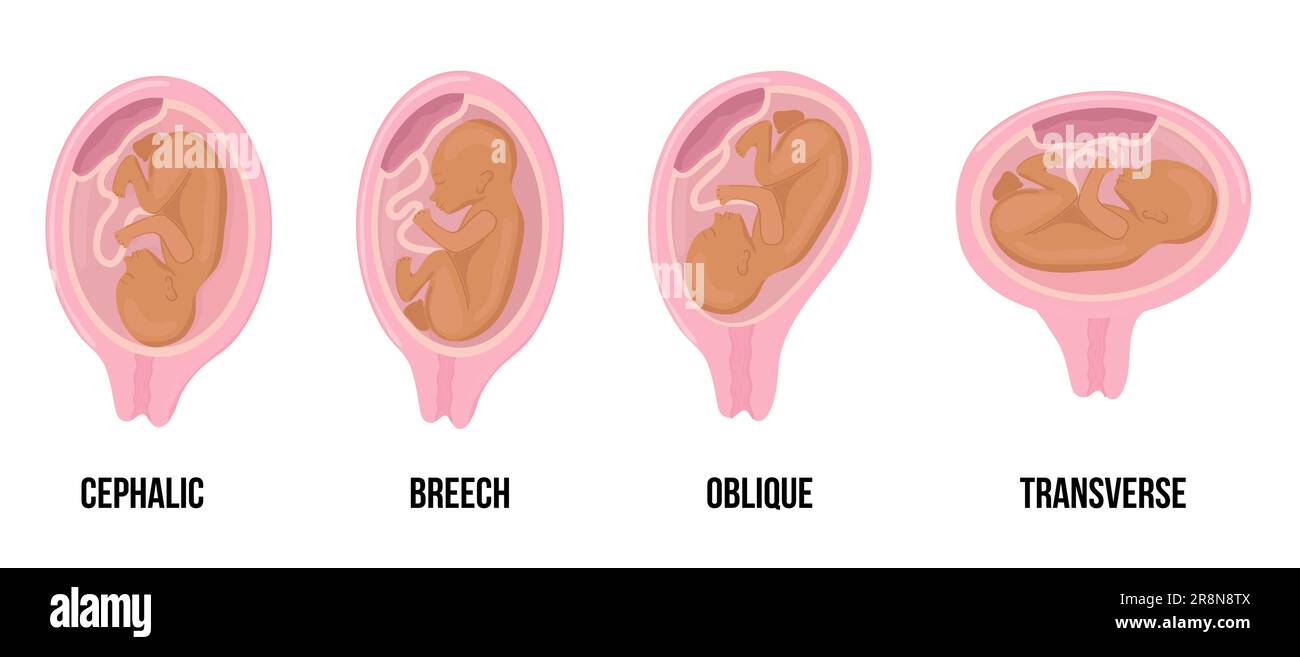

Latin arabian brown skin baby. Different wrong baby positions in uterus during pregnancy. Cephalic, Breech, transverse, Oblique lies. Colored medical Stock Vectorhttps://www.alamy.com/image-license-details/?v=1https://www.alamy.com/latin-arabian-brown-skin-baby-different-wrong-baby-positions-in-uterus-during-pregnancy-cephalic-breech-transverse-oblique-lies-colored-medical-image556116986.html

Latin arabian brown skin baby. Different wrong baby positions in uterus during pregnancy. Cephalic, Breech, transverse, Oblique lies. Colored medical Stock Vectorhttps://www.alamy.com/image-license-details/?v=1https://www.alamy.com/latin-arabian-brown-skin-baby-different-wrong-baby-positions-in-uterus-during-pregnancy-cephalic-breech-transverse-oblique-lies-colored-medical-image556116986.htmlRF2R8N8TX–Latin arabian brown skin baby. Different wrong baby positions in uterus during pregnancy. Cephalic, Breech, transverse, Oblique lies. Colored medical